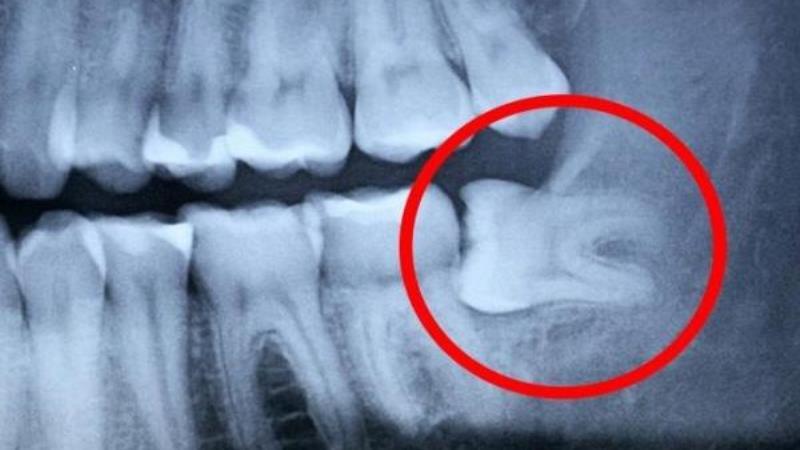

| Прорезывание зубов мудрости (ретинированные зубы) | Тупая, ноющая боль в области челюсти, которая может отдавать в висок, ухо, горло. Отек и воспаление десны вокруг прорезывающегося зуба. Ограничение открывания рта. | Обратиться к стоматологу-хирургу для оценки ситуации и, возможно, удаления зуба мудрости. |

| Киста или гранулема на корне зуба | Часто протекает бессимптомно, но при обострении может вызывать ноющую боль, отек, повышение температуры. Боль может иррадиировать в голову. | Обратиться к стоматологу для диагностики (рентген) и лечения (эндодонтическое лечение, хирургическое удаление). |

К показаниям для удаления относятся следующие факторы: неправильное положение и наклон зуба, смещение соседних зубов, развитие перикоронита, а также кариозные изменения.

Дополнительно могут быть назначены рентгенологические исследования. Рентгенография позволяет визуализировать состояние зубов и челюстных костей, выявить скрытые проблемы, такие как кисты или инфекции, которые могут быть причиной головной боли. В некоторых случаях может потребоваться компьютерная томография для более детального изучения состояния зубочелюстной системы.